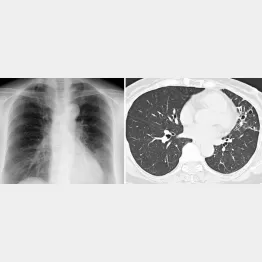

咳や痰が続きつらいなら疑うべき…「気管支拡張症」とは?

これらの症状が見られる病気のひとつに気管支拡張症がある。この病気は、何らかの要因で気管支に傷ができ、そこに細菌が定着。過剰な免疫反応で炎症が慢性化し、結果的に気管支が拡張する。